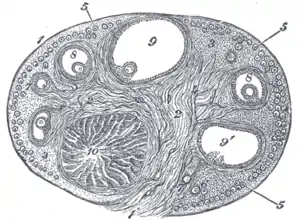

Section of the ovary. 1. Outer covering. 1’. Attached border. 2. Central stroma. 3. Peripheral stroma. 4. Bloodvessels. 5. Vesicular follicles in their earliest stage. 6, 7, 8. More advanced follicles. 9. An almost mature follicle. 9’. Follicle from which the ovum has escaped. 10. Corpus luteum. | |